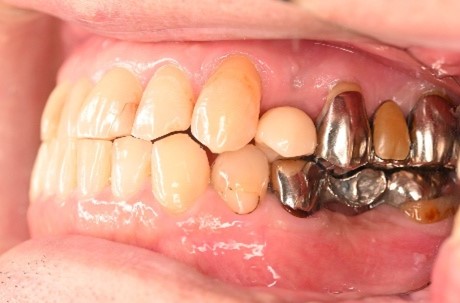

Before

▼初診時に使用していた部分入れ歯を装着したところ

▼インプラント埋入前